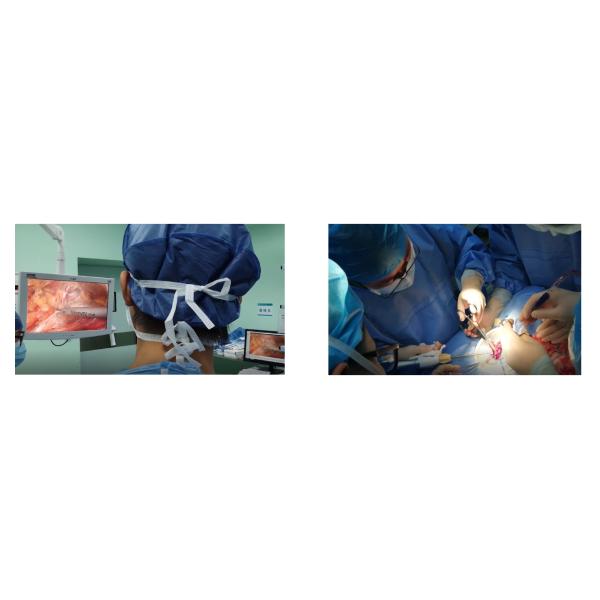

Disposable Ultrasonic Scalpel System Scissor Type Scalpel Images |